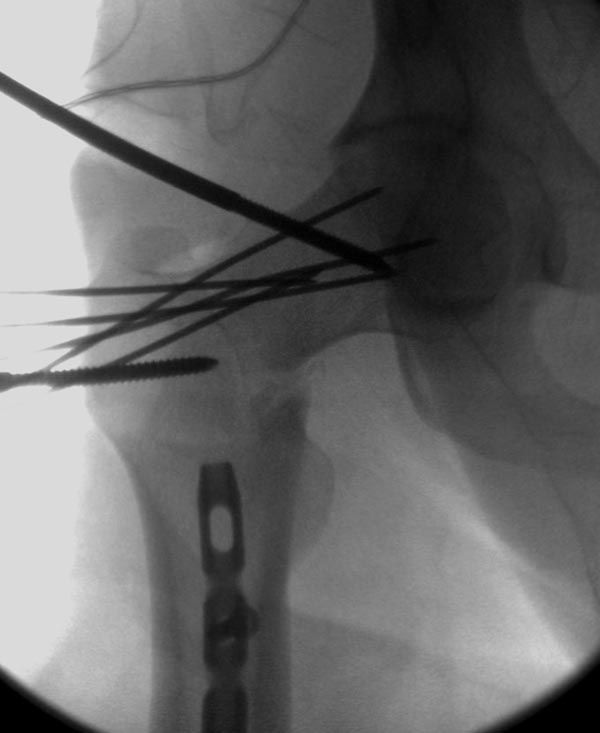

Здесь выставлен ренгенограммы больного, ему 21, травму получил в результате высокоскоростной погони на украденной машине, которая закончилась смертью трех остальных “боевых комрадов”. Начатую коллегой открытую операцию на шейке пришлось закончить мне, установкой винтов и ретроградной фиксацией бедра. Выписка в обычное сроки и наблюдался амбулаторно. Каждый раз напоминали о возможности осложнений ввиде несращения! По истечению 4 месяцев появились признаки варусной деформации. На СТ срезах несращение шейки и бедра. Риминг, замена на более толстый гвоздь и вальгусная остеотомия.